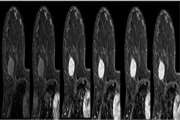

بررسی مقایسه ای و تعیین میزان همبستگی تغییرات یافته های MRI عضله با علایم بالینی وپاراکلینیک طی پیگیری 6 ماهه در بیماران مبتلا به میوپاتی التهابی مراجعه کننده به بیمارستان شریعتی از سال 1397 تا 1399 1404/01/17 - 11:11